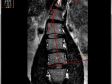

По предоставленным Вами данным МРТ от 29.01.2016 без динамики (!) (улучшения или ухудшения) по сравнению с данными МРТ от 22.07.2015 года:

- Задне-срединная протрузия L5\S1 , вероятно с обызвествлениями ( в народе говорят "старый радикулит" или "радикулит за польским часом" , то есть речь идет не о свежем разрыве фиброзного кольца диска)

- Сколиотическая деформация поясничного отдела позвоночника 3 степени (L1-L4) с вершиной на уровне L1-2

- "Скрученный таз "(Формирование скрученного таза как реакция на нарушение функции органов малого таза (матки, простаты, мочевого пузыря, толстого кишечника)

С целью уточнения диагноза рекомендуется Рентген Компьютерная Томография пояснично-крестцового (выявление обызвествлений) и шейнного отдела позвоночника , особенно зону так называемых "суставов головы" (верхне - шейный отдел C0 - C2)